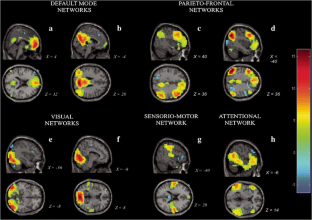

Generalized Fixation-off Sensitivity (CGE-FoS) patients present abnormal EEG patterns when losing fixation. In the present work, we studied two CGE-FoS epileptic patients with simultaneous EEG-fMRI. We aim to identify brain areas that are specifically related to the pathology by identifying the brain networks that are related to the EEG brain altered rhythms. Three main analyses were performed: EEG standalone, where the voltage fluctuations in delta, alpha, and beta EEG bands were obtained; fMRI standalone, where resting-state fMRI ICA analyses for opened and closed eyes conditions were computed per subject; and, EEG-informed fMRI, where EEG delta, alpha and beta oscillations were used to analyze fMRI. Patient 1 showed EEG abnormalities for lower beta band EEG brain rhythm. Fluctuations of this rhythm were correlated with a brain network mainly composed by temporo-frontal areas only found in the closed eyes condition. Patient 2 presented alterations in all the EEG brain rhythms (delta, alpha, beta) under study when closing eyes. Several biologically relevant brain networks highly correlated (r > 0.7) to each other in the closed eyes condition were found. EEG-informed fMRI results in patient 2 showed hypersynchronized patterns in the fMRI correlation spatial maps. The obtained findings allow a differential diagnosis for each patient and different profiles with respect to healthy volunteers. The results suggest a different disruption in the functional brain networks of these patients that depends on their altered brain rhythms. This knowledge could be used to treat these patients by novel brain stimulation approaches targeting specific altered brain networks in each patient.

Fig. 1

Fig. 2

Fig. 3

Fig. 4

Fig. 5

Fig. 6

Fig. 7

Fig. 8

Fig. 9